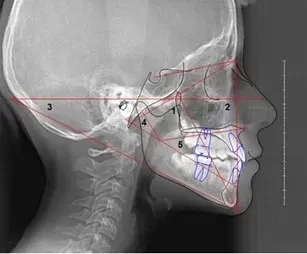

Possiamo ottenere tutte le informazioni che servono per decidere se serve l’apparecchio ortodontico per i vostri figli e quale sia l’approccio migliore.

È utile per l’ortodonzia?

Sì, aiuta a definire se è necessario un apparecchio e quale trattamento adottare.